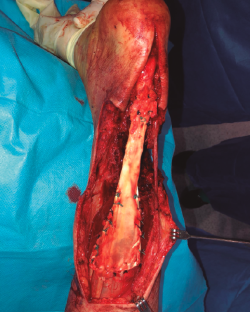

Figura 5. Fotografía intraoperatoria. Muestra la sutura proximal de tipo Krackow y la anastomosis distal con muñón de tendón remanente.

La fijación se obtuvo a través de una sutura de tipo Krackow en la unión miotendinosa proximal y sutura término-terminal a nivel distal, al existir muñón distal suficiente (Figura 5). De forma simultánea, se realizó la cobertura cutánea con un colgajo fascio-cutáneo vascularizado del muslo del paciente (Figuras 6A, 6B y 6C).